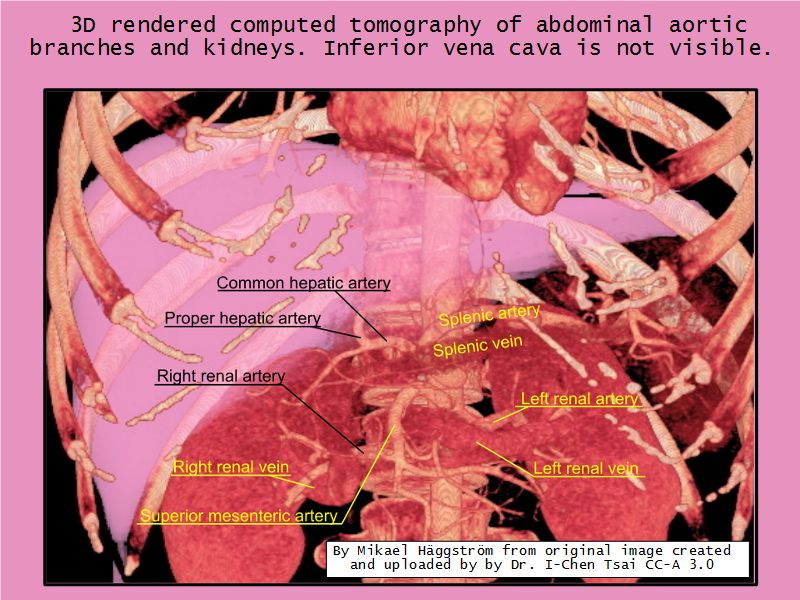

Blood flow

- Efferent arteriole

- Smooth muscle in media

- Capillaries

- Fenestrated

- Afferent arteriole

- Smooth muscle in media